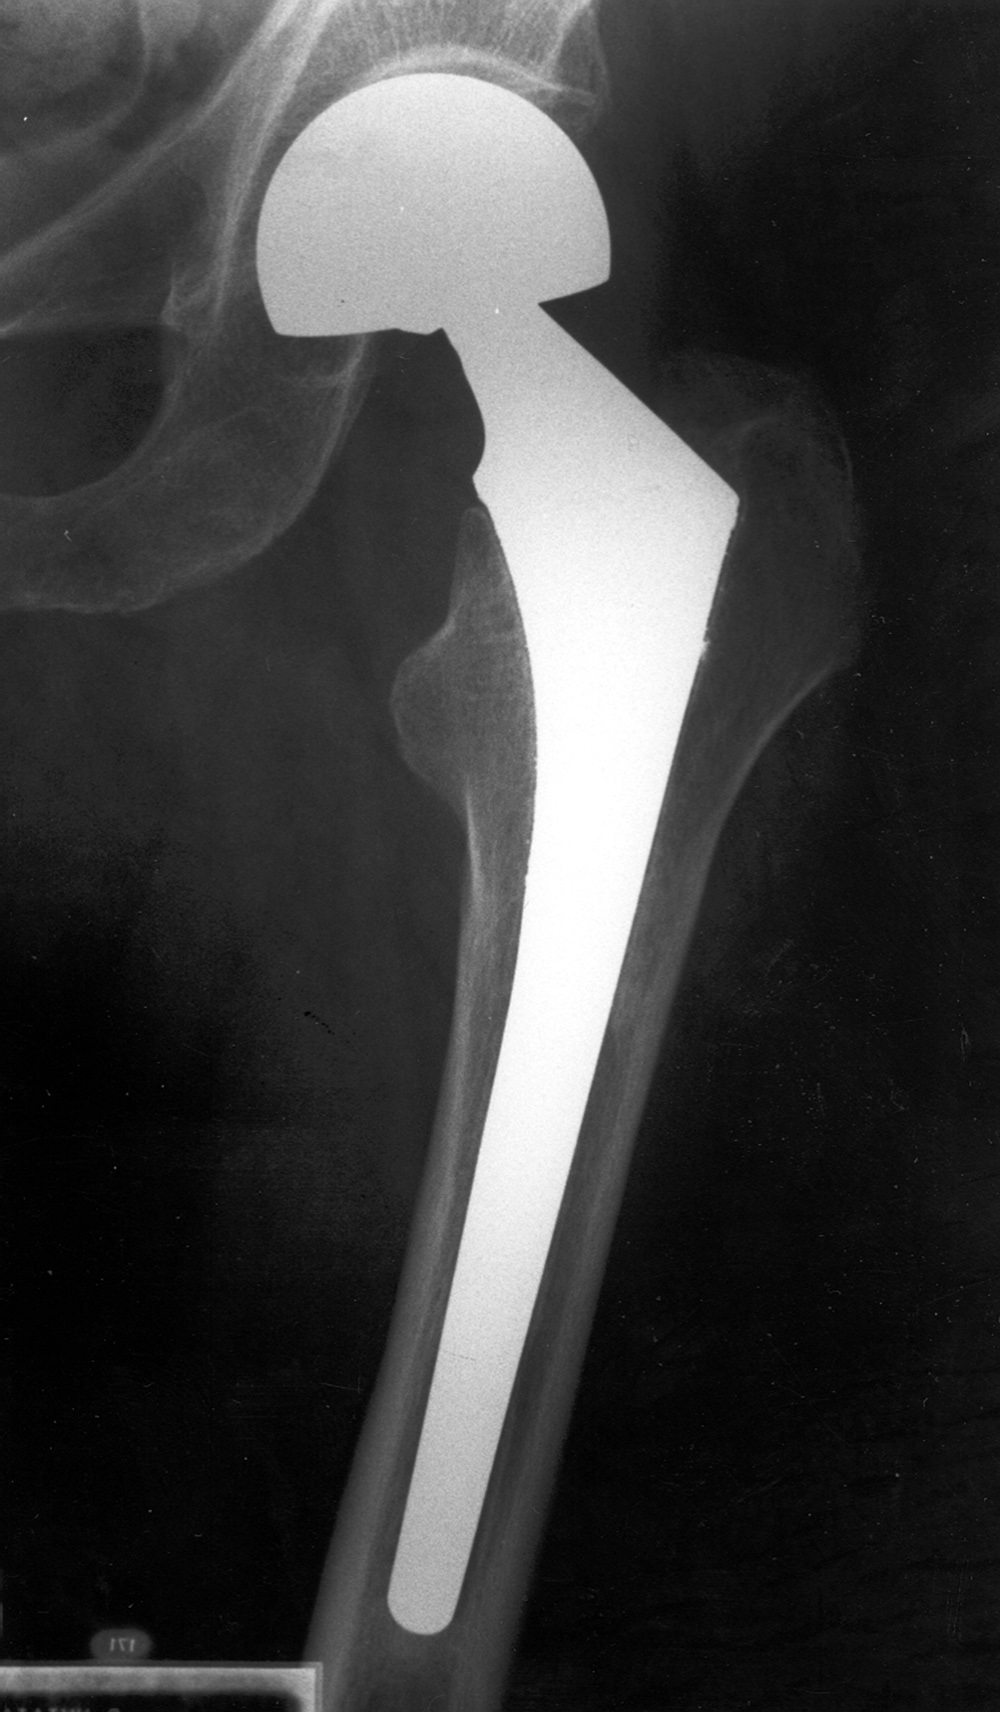

| Unipolar hip hemiarthroplasties (endoprostheses) |

Unipolar hip hemiarthroplasty (endoprosthesis) with a cemented femoral component |

Modular non-cemented unipolar hip hemiarthroplasty (endoprosthesis) |

| These are single piece prostheses press fit into the native acetabulum and the native femur. From Benjamin, 1994 |

Note the collar abutting the femoral calcar. From Benjamin, 1994 |

Note the collar abutting the femoral calcar. |